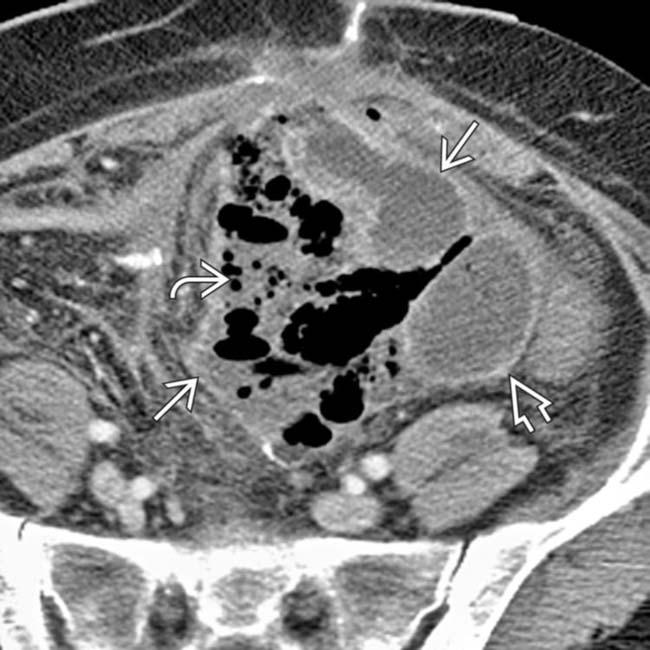

Abdominal Abscess Clinical Gate Abscess After Surgery Abscesses can occur anywhere in the abdomen and retroperitoneum. Postoperative wound infections are a common complication following surgery, characterized by complex and multifactorial pathophysiology. Have an injury, like a gunshot wound or stab wound, which lets bacteria into your belly. Develop an infection after abdominal surgery. Several factors can cause them, including infection of a surgical incision, fluid leakage from. Abscess After Surgery.